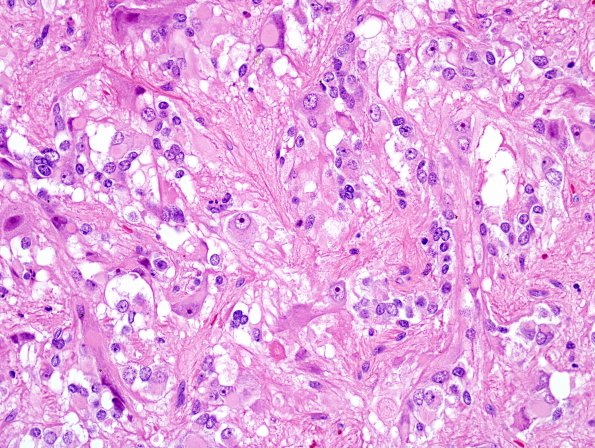

8B7 PA & GGL diffn (Case 8)  (ggl) H&E A1

Higher magnification image of the second area. (H&E)